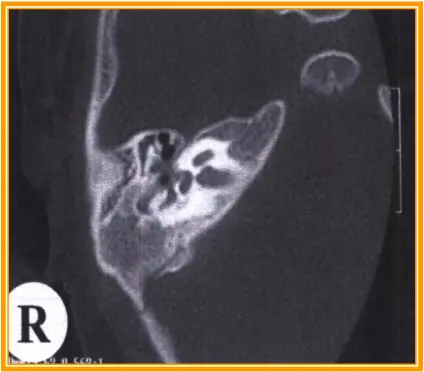

- 中耳炎的特征性——波Ⅰ潜伏期延长

右侧Ⅰt=2.05ms明显较左侧延长

声导抗测试无峰,颞骨CT显示中耳腔有高密度影